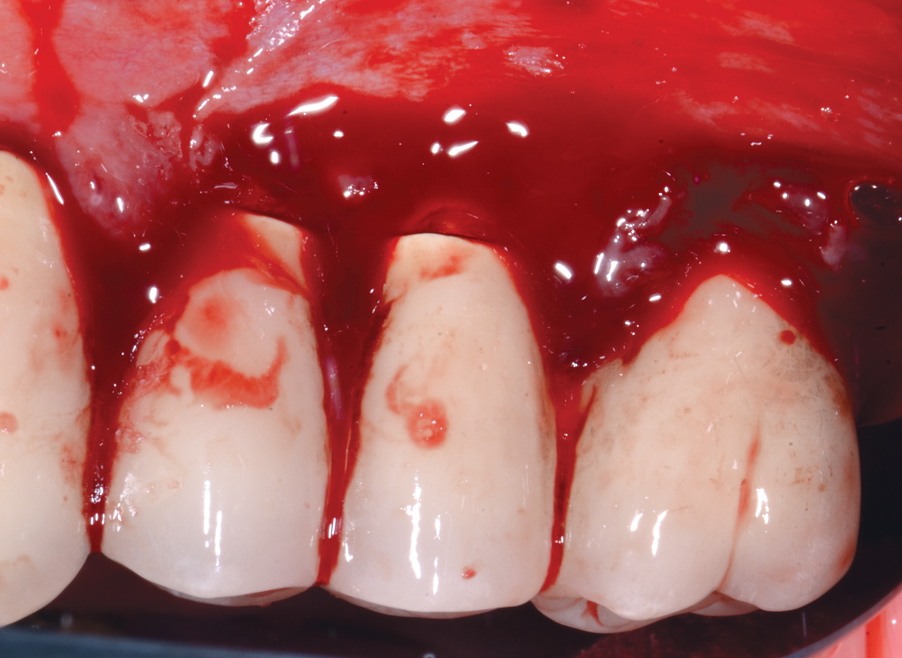

Dental implants have revolutionized the way in which clinicians treat and restore partially and fully edentulous patients and have demonstrated success for managing a broad range of clinical dilemmas. While implants have been highly predictable and have achieved long-term success, they are not immune from complications associated with improper treatment planning, poor surgical and prosthetic execution, material failure, and inadequate or infrequent maintenance. Among these problems are the biologic complications of peri-implant mucositis and peri-implantitis, which are inflammatory conditions in the soft and/or hard tissues surrounding dental implants (Figure 1 through Figure 4).1,2

Fig 8. A mucogingival deformity existed on the premolar implants.

Figure 8

Fig 9. A full-thickness flap was elevated and the surfaces decontaminated with air-powder abrasion with glycine-based powder and citric acid.

Figure 9

Fig 10. An autologous subepithelial connective tissue graft was secured in the area with 6-0 chromic gut suture using an interrupted technique. Recombinant platelet-derived growth factor was applied to both the implant surfaces and the graft.

Figure 10

Fig 12. Three years following treatment, stability was achieved with the soft tissue.

A thinner gingival biotype is also a sign that the underlying bony housing may be thin; this relates to the concept of blood supply to maintain bone height. In thinner bone that is subjected to inflammation, adequate blood supply may not be present to maintain its viability. Where gingiva is thin or absent at the time of implant placement, strong consideration must be given to proactively grafting these sites with soft tissue just prior to restoration or at the earliest signs of inflammation to protect the underlying bone. Figure 8 through Figure 12 highlight such a situation.